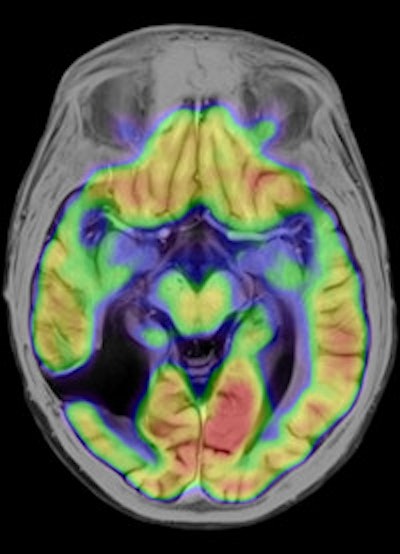

Left: To improve the precision of spatial registration, the Biograph mMR system collects MR and PET data simultaneously from a single frame of reference. The result is a combined MR and PET scan acquired at the same point in time and reflecting the same point in the physiologic processes such as respiration. Right: The benefits of MRI in the study of neurological diseases are well-known and established, and it can lead to a better understanding of neurological pathologies. Images courtesy of Siemens.Philips has been working on its latest MR technology for almost as long as the search for a practical PET/MR hybrid. After an eight-year development project, the company is promoting its Ingenia 1.5- and 3-tesla systems, which it describes as the world's first digital broadband MR unit. This incorporates dStream architecture, which digitizes the signal directly in the coil. Vendors have been looking for ways to shorten the analogue part of the signal processing pathway because this offers the potential for reducing signal loss and noise. The Philips approach goes further by digitizing the signal within the coil itself and transporting it via a fiber-optic cable to the acquisition electronics contained in the scanner cabinet, explained Maurits Wolleswinkel, global lead for MR marketing.